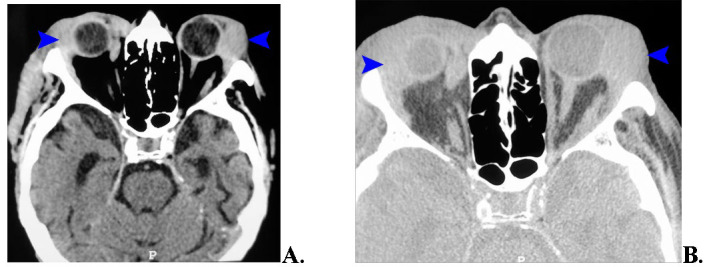

Lacrimal gland lymphomas are rare orbital tumors, constituting a minor fraction of all orbital and ocular adnexal malignancies. This case study presents an 83-year-old male with bilateral lacrimal gland tumors, more prominent in the left orbit, causing decreased visual acuity, red eye, excessive tearing, and diplopia. Initial ophthalmological evaluations and imaging suggested bilateral lacrimal gland lymphoma, confirmed by histopathology as diffuse large B-cell non-Hodgkin lymphoma of the MALT type. Due to the significant tumor size and risk of visual function loss, surgical intervention was performed, followed by corticosteroid therapy. Postoperatively, a marked improvement in symptoms and a reduction in tumor size were observed. This case underscores the importance of comprehensive diagnostic approaches, including clinical, imaging, and histopathological evaluations, highlighting the need for a multidisciplinary approach in managing rare orbital tumors like lacrimal gland lymphoma. The patient's postoperative and follow-up care included oncological management to monitor and ensure long-term disease control and patient well-being. Abbreviations: RE = right eye, LE = left eye, CT = Computer tomography, MRI = Magnetic Resonance Imaging, TOD = intraocular pressure of right eye, TOS = intraocular pressure of left eye, US = ultrasound.